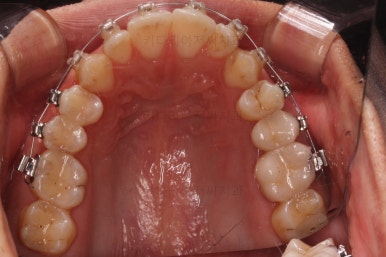

초진 시 입안의 모습입니다.

앞니가 약간 삐뚠 것 말고는 큰 문제는 없어보이네요.

장치를 부착했습니다.

이번 부산연제구교정 환자분이 선택한 장치는 엠파워 클리어라고 하는 자가결찰 세라믹 장치입니다.

최대한 빠른 시일 내에 치열을 가지런하게 해주고 미니스크류를 많이 식립하게 됩니다.